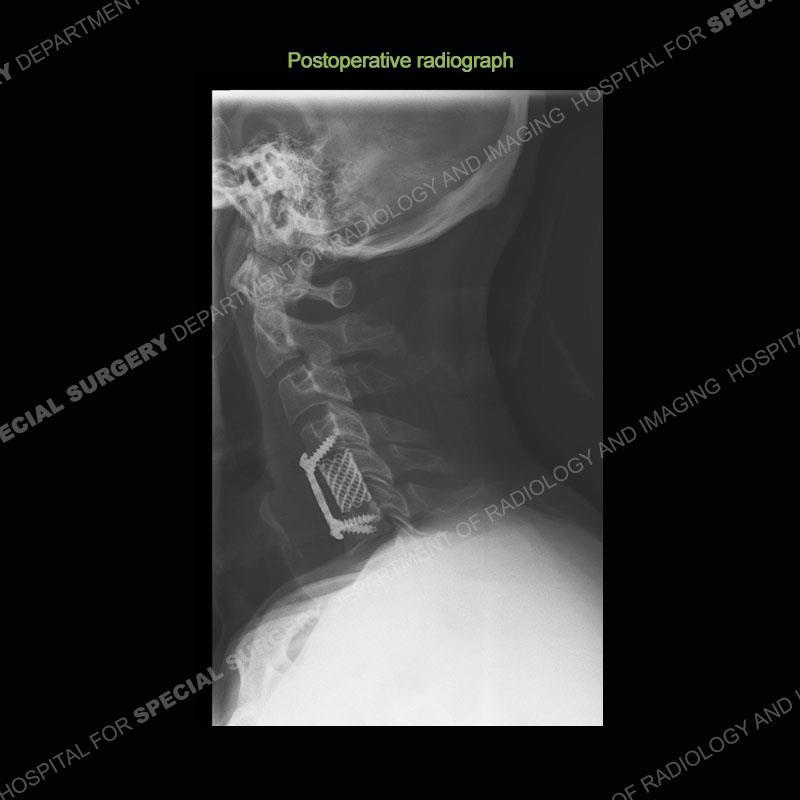

Spontaneous RPA in the non-immunocompromised, adult population is an extremely rare occurrence. RPA most frequently occurs in young children and most typically after a URI. It may be associated with torticollis in Grisel syndrome. In the adult population, the pathomechanism is not well understood with some suggesting a hematogenous spread or perhaps a seeding from the adjacent aerodigestive tract. The abscess as in this case can extend to involve the vertebral column and then the neural elements. At times, this process can be treated with antibiotic therapy alone but when there are neurologic symptoms and especially progression of neurologic symptoms, surgical intervention is warranted. In this case, given the extent of the process and the patient’s clinical situation, a corpectomy with fusion was performed in addition to antibiotics.